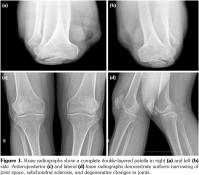

A 42-year-old male patient was examined due to gait difficulty and pain in hip and knee joints bilaterally and low back. He declared that he could walk independently, yet he had some difficulties in walking on undulating surfaces or climbing up stairs. Medical and family history was noncontributory. He was 168 cm tall and weighed 78 kg. Physical examination revealed severe restriction of range of motion in hip joints, crepitation in knee joints, hyperextension position of the first metacarpophalangeal joint, and deviation of the thumbs. Adam’s test for scoliosis was positive and lumbar motions were limited as well. Minimal joint effusion was detected in knee joints as well. Knee radiographies showed double- layered patella (DLP), generalized degenerative changes, scoliosis, and circumferential radiopaque lesion around the right hip joint (calcification of the iliopsoas bursa) (Figures 1 and 2). Magnetic resonance imaging designated the association between the quadriceps tendon and patella (Figure 3). Laboratory investigations including erythrocyte sedimentation rate and C-reactive protein, calcium, phosphate, and alkaline phosphatase levels were all within normal limits. Overall, the patient was diagnosed with secondary OA due to MED and referred to another center for further genetic analysis. A written informed consent was obtained from the patient.

Our patient with clunking in the knees had DLP bilaterally, which was reported previously in the literature.(8) DLP is a type of bipartite patella and caused by a septum dividing the patella into segments. It can be seen completely or partially. In general, DLP is associated with MED; however, it is reported in nondysplastic subjects as well.(9) Our patient had the total form of DLP. Magnetic resonance imaging showed that the distal part of the DLP was responsible for the extensor mechanism of the knees. This condition is important because the functional part could be indicative for a possible surgical procedure or functionality of the knee movements.